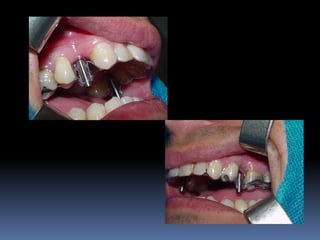

Guia Funcional

•Posicionamento das perfurações

•Dimensões verticais e oclusão

•Transferência dos intermediários nas moldagens

•Carga imediata

Duplicação de prótese

Guia funcional para carga imediata